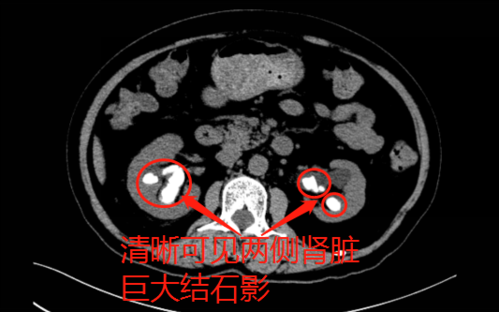

肾铸型结石图片,肾结石图片清晰图片

充满型肾铸型结石的微创手术治疗

经专家的进一步详细检查,患者确诊为双肾多发性结石,含铸型结石,左肾

右肾铸型结石

肾结石图片清晰图片

铸型结石图片

铸型肾结石

铸型结石